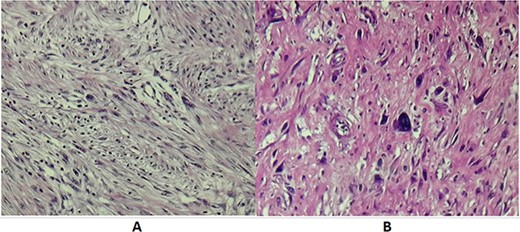

Histopathological examination of operative specimens showed focal areas of necrosis accounting for less than 50% of the tumor mass. Tumor cells were spindle shaped, pleomorphic and had moderate to severe atypia. Mitotic figures were abundant, counting 1–2 mitosis per 10 CFG. Surgical margins were free of disease. Renal parenchyma, renal pelvis and ureter were free of neoplasia. Pathology turned out to be RPL Grade II according to the French staging system for sarcoma tumors FNLCC (Fig. 3).

(A) Microscopic examination showing spindle cells with elongated hyperchromatic nuclei and arranged in interlacing bundles of (HE X 200). (B) Tumor cells showing nuclear atypia and eosinophilic cytoplasm (HE X 400).